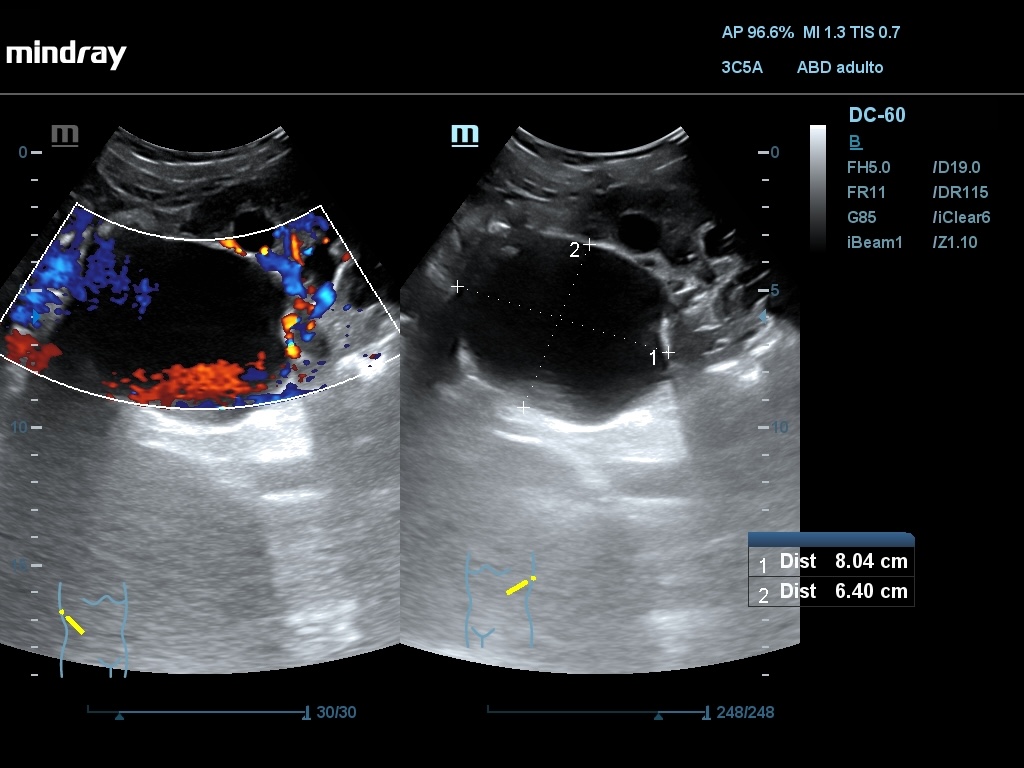

Ecografía abdominal: Se observan varios quistes simples a nivel hepático, siendo el mayor de 52,4 mm, en ambos riñones siendo el mayor de 77 x 83 mm en RD y de 80 x 64 mm en RI. En hipogastrio se observa imagen redondeada, anecogénica, con sombra posterior, de borde liso y fino, no tabicada, de aprox. 161 x 142 mm y otra de características similares de 74 x 54 mm.

Diagnóstico diferencial: Se debe diferenciar principalmente del Cistocarcinoma seroso, que a nivel ecográfico aparece como multiloculado, con proyecciones papilares y polos sólidos captantes. Pueden ser bilaterales y acompañarse de ascitis. Pueden asociar implantes peritoneales.